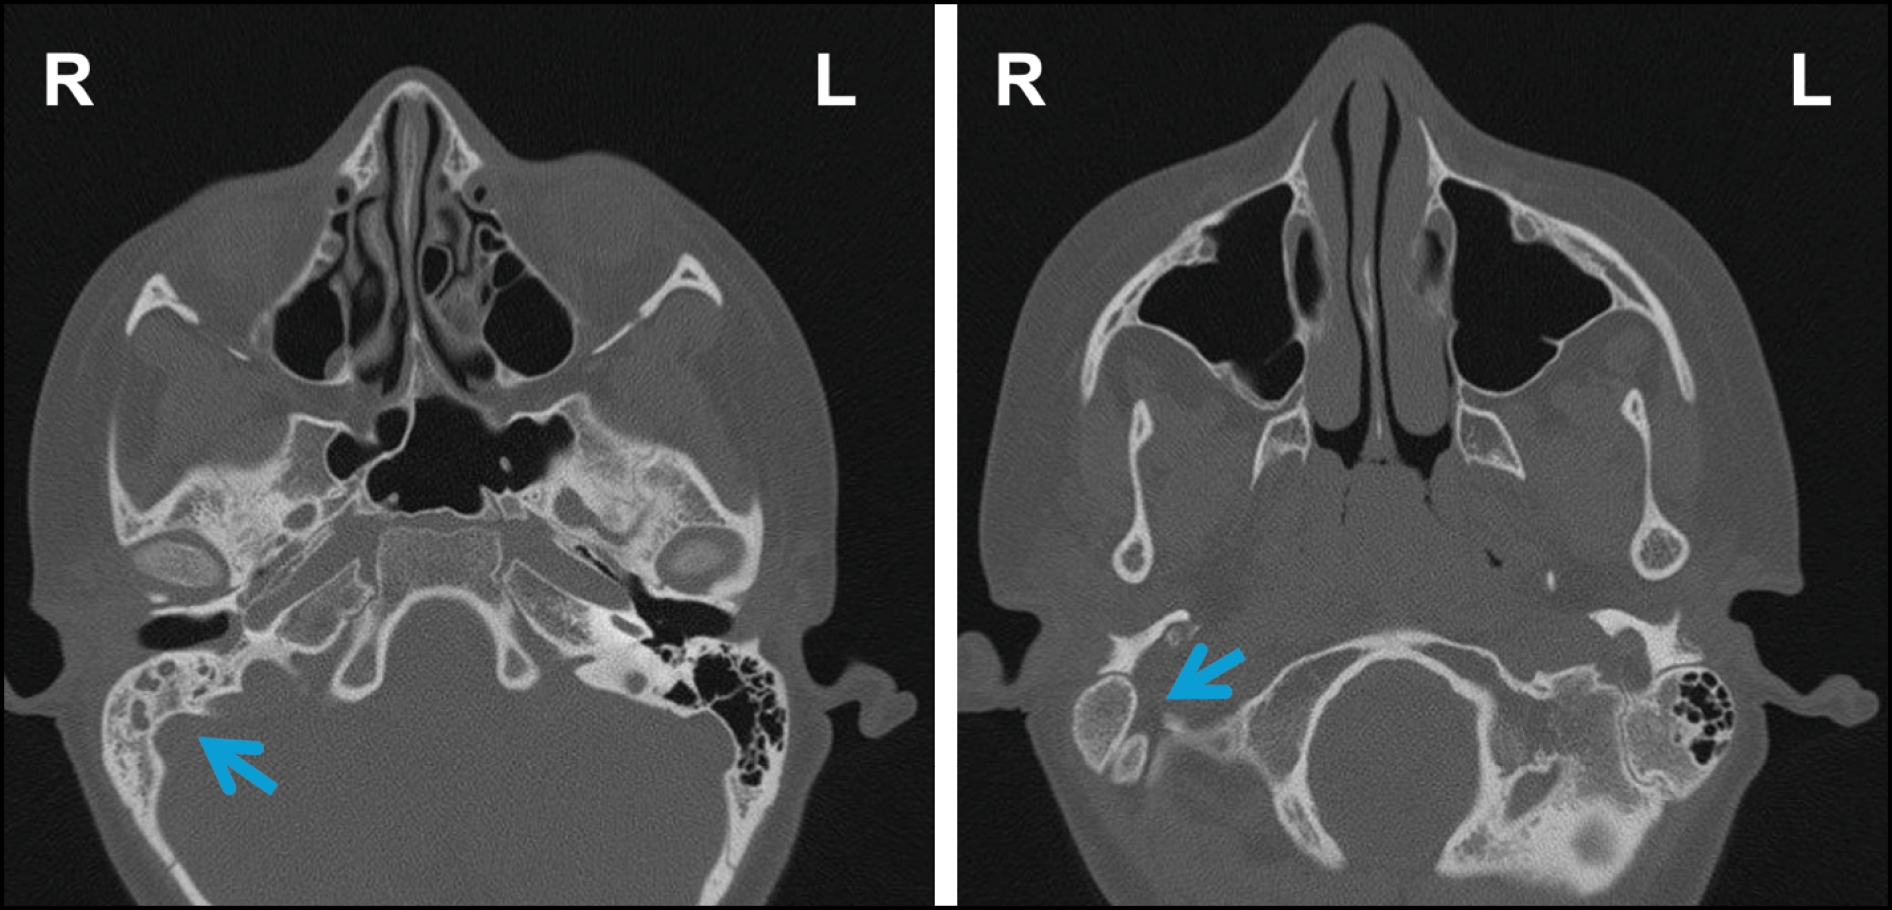

A high-resolution computed tomography (CT) scan (Figure 1) of the temporal bones, combined with clinical and microbiological findings, led to the diagnosis of suppurative AOM complicated by otomastoiditis.

Figure 1 - Axial high-resolution CT scans of the temporal bones and paranasal sinuses, without contrast, showing inflammatory obliteration of the right middle ear and mastoid cells, without bone erosion or ossicular damage. The contralateral ear and paranasal sinuses are unremarkable. Pneumatization of the paranasal sinuses is within normal limits.